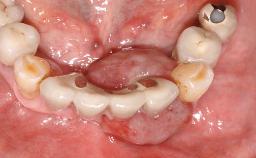

The case concludes with the presentation of the final prosthesis and the esthetic outcome, demonstrating stable soft tissue conditions and stable bone crest levels at the 3-year follow-up.

Abutment Type Standard

Prosthesis Type FDP

Esthetic Risk Assessment